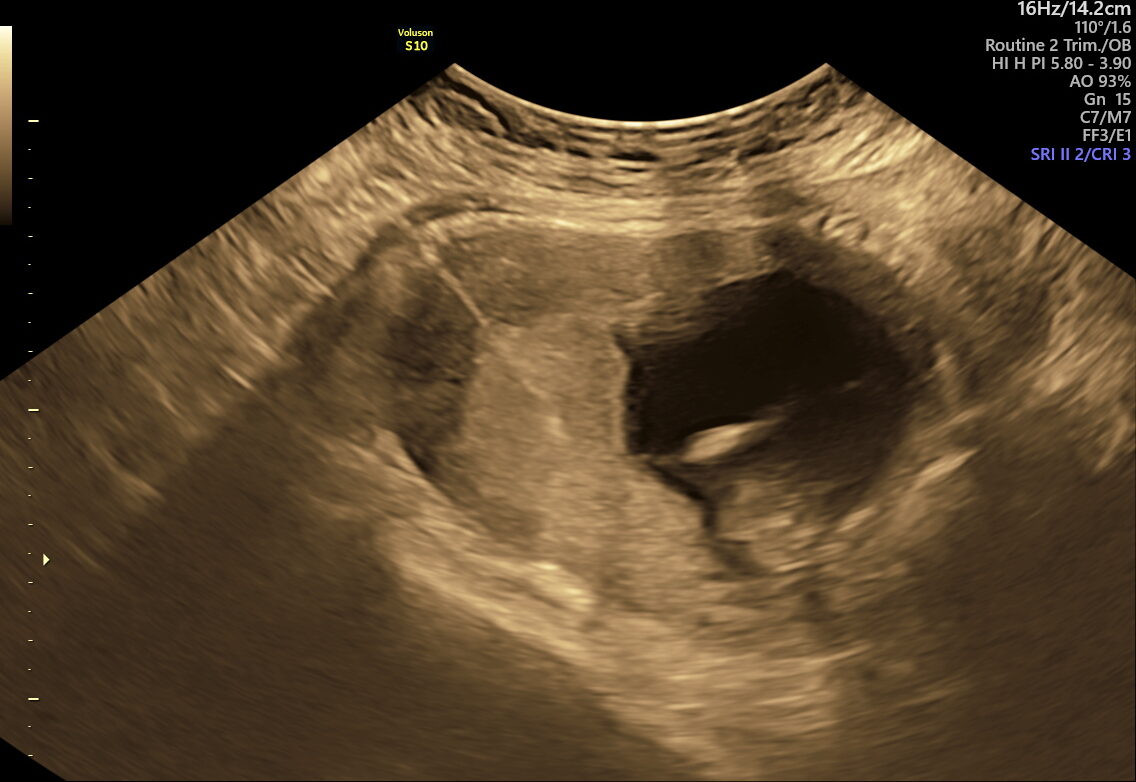

CVS is an early genetic test done between 10–13 weeks of pregnancy. A tiny sample of placental tissue (chorionic villi) is taken to analyze the baby’s chromosomes. CVS provides early answers for families at risk of genetic disorders or who have had abnormal screening results. Unlike screening tests that estimate risk, CVS provides clear, laboratory-confirmed answers. It is performed in the first trimester, making it one of the earliest opportunities for definitive genetic diagnosis during pregnancy.

CVS is typically performed between 10–13 weeks of pregnancy.

- High-resolution ultrasound guidance ensures accurate sampling and minimal risk